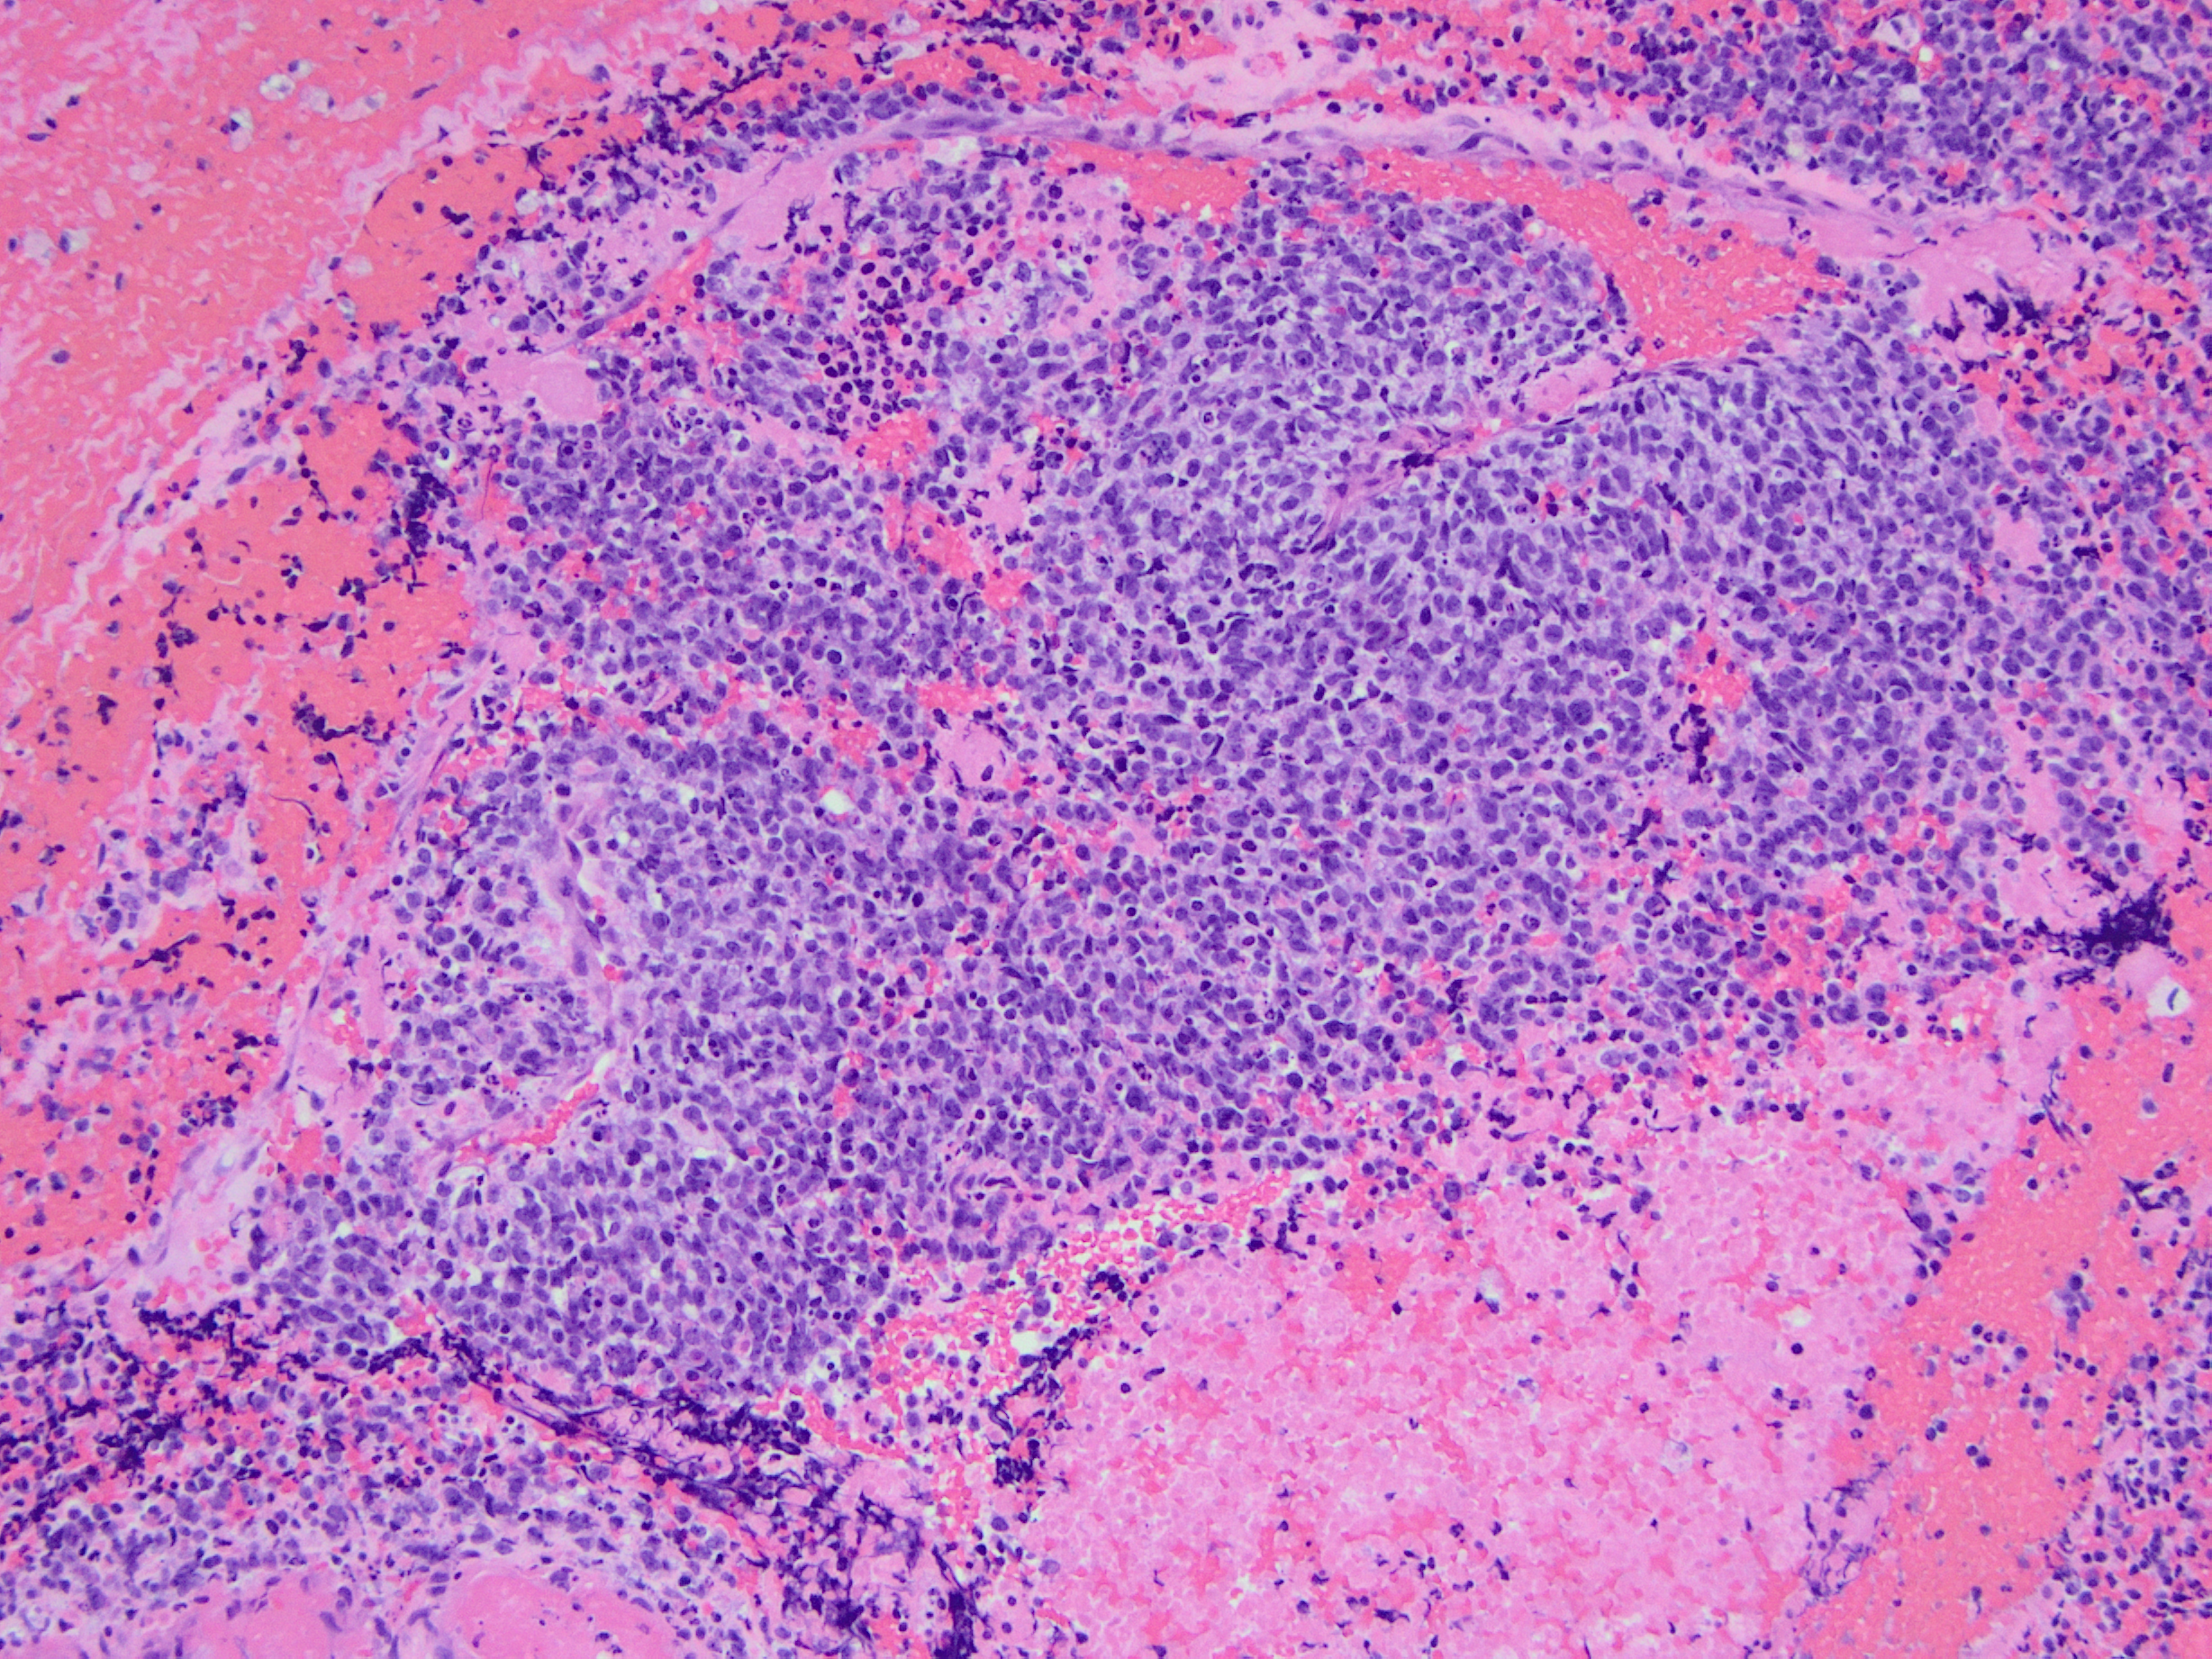

The patient is a 71-year-old female with a lower extremity weakness and a lobulated, solid contrast enhancing intradural intramedullary lesion at C6-T1 levels on MRI. A CT chest, abdomen, and pelvis demonstrated small lesions in the lungs, breast, and liver concerning the possible metastatic disease.

The tumor shows strong cytoplasmic positivity for CD99. The tumor cells are negative for chromogranin, synaptophysin, CK7, CK20, pan-CK, GATA3, HMB45, PAX8, TTF1, p40, and SOX10:

CD99  HE 10X Capture485

CIC-DUX4 rearranged sarcoma is a small blue round cell tumor resembling Ewing sarcoma. In addition to small blue round cells morphology, CIC rearranged sarcoma may also show focal areas of spindling and epithelioid/rhabdoid phenotype, with frequent myxoid stromal changes. Similar to Ewing sarcoma, it also shows strong cytoplasmic and membranous positivity of CD99. Patient age at presentation ranges from 6 to 70 years (mean age: 32 years). Most of the time it arises in the soft tissue of the trunk and extremities.  Overall survival is worse than Ewing sacrcoma.